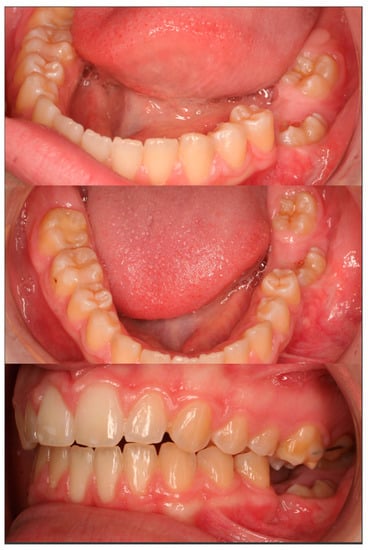

2. Case Presentation